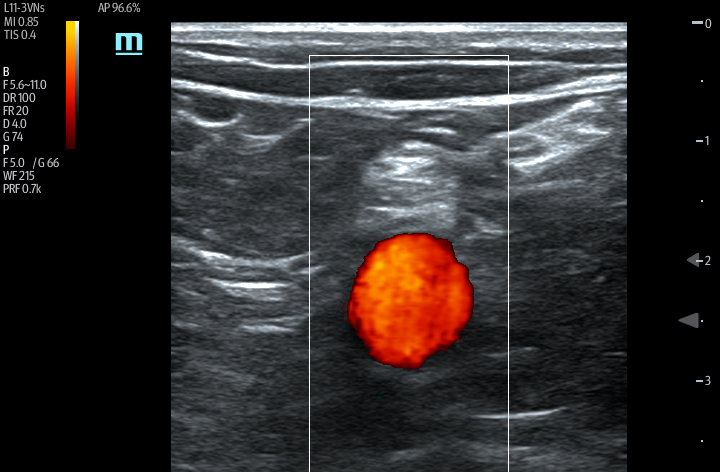

The TE7 Ultrasound System Crystal Series 2.0 is the system of choice from routine point-of-care exams to extreme situations when every second counts. With best-in-class image quality, a sleek form factor, and breakthrough needle visualization advancements, the TE7 System is designed to provide superior performance for rapid, confident exams and procedures in the fast paced, point of care environment.